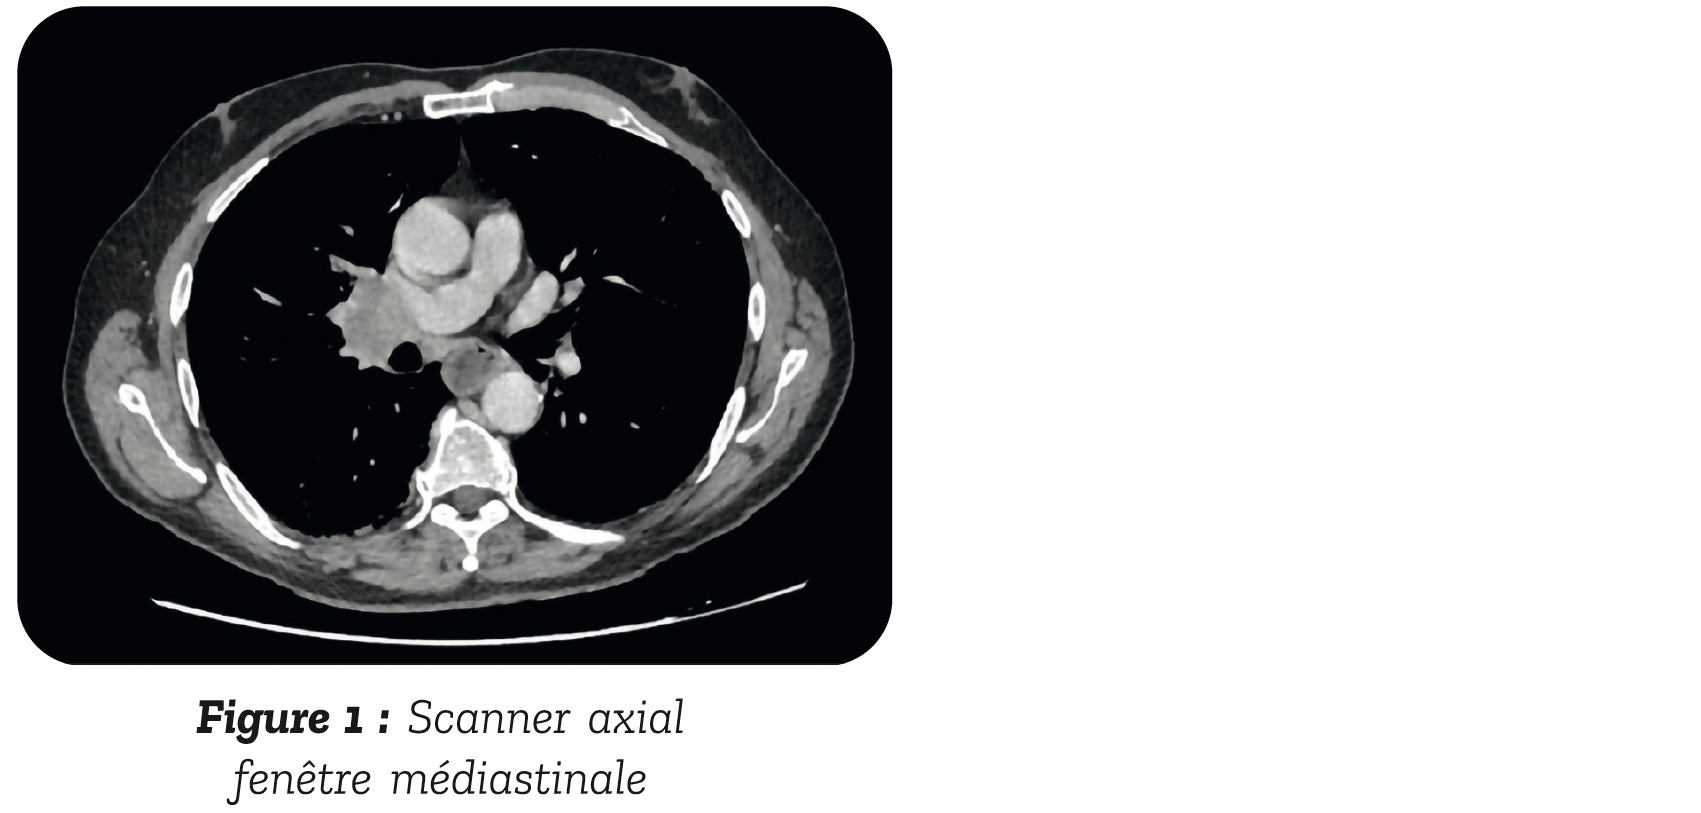

Dans le cadre des symptômes neurologiques, un scanner thoraco- abdomino-pelvien injecté est réalisé et ne montre pas de compression médullaire. En revanche, il met en évidence une masse médiastin hilaire droite de 42 x 32 mm (figure 1 et 2), avec dilatation œsophagienne.

Il a ensuite été transféré en pneumologie pour l'exploration de la masse pulmonaire où une fibroscopie bronchique avec biopsie Trans trachéale a permis d'identifier un carcinome bronchique à petites cellules. Dans le cadre du bilan d'extension, un TEP-TDM a été réalisé qui retrouvait une hyperfixation de la masse pulmonaire à droite, sans autre site d'hy- permétabolisme et l'IRM cérébrale ne retrouvait pas de lésion secondaire.